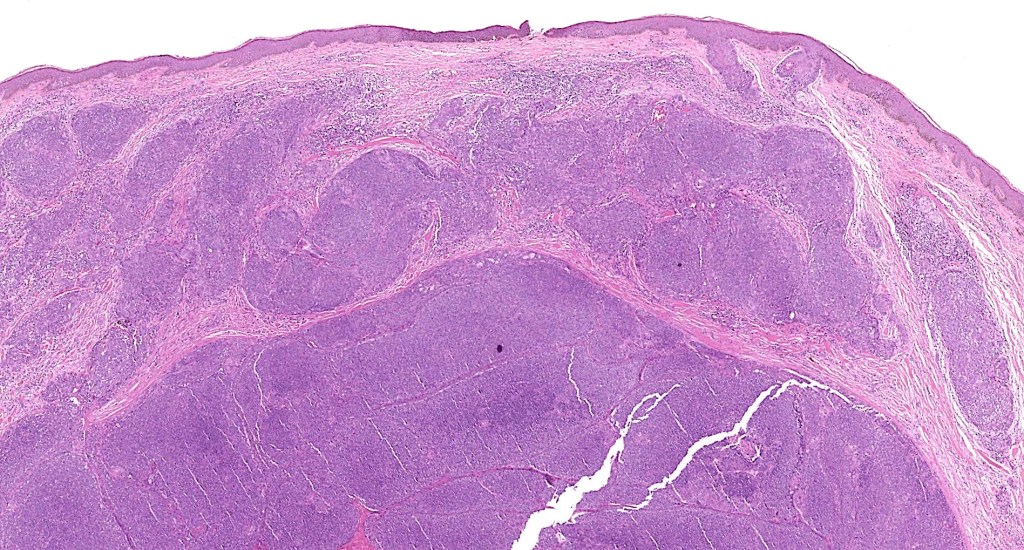

•Dermal generally circumscribed tumor nodule (less often it may show an infiltrative border)

•Absence of an epidermal connection